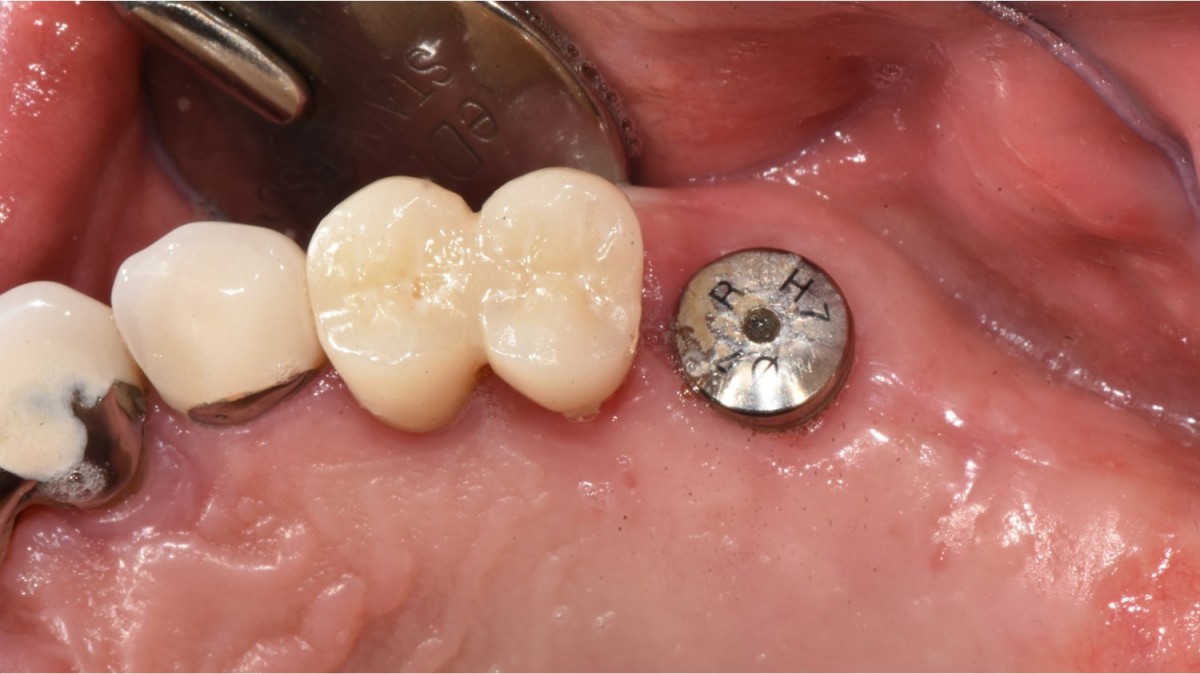

Immediate implant placement in the left molar of the maxilla.

A 57-year-old male patient recently underwent

implant restoration on the maxillary right molar. This time, he is scheduled to

proceed with the left molars. (ARUM implant system)

▲2 implants were placed. ArumDentistry NB1 5*10 (30Ncm) in the 1st molar and 5*10 (10Ncm) in the 2nd molar.